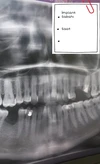

Dentist Muhammet Hakkı Bostan

Dentist